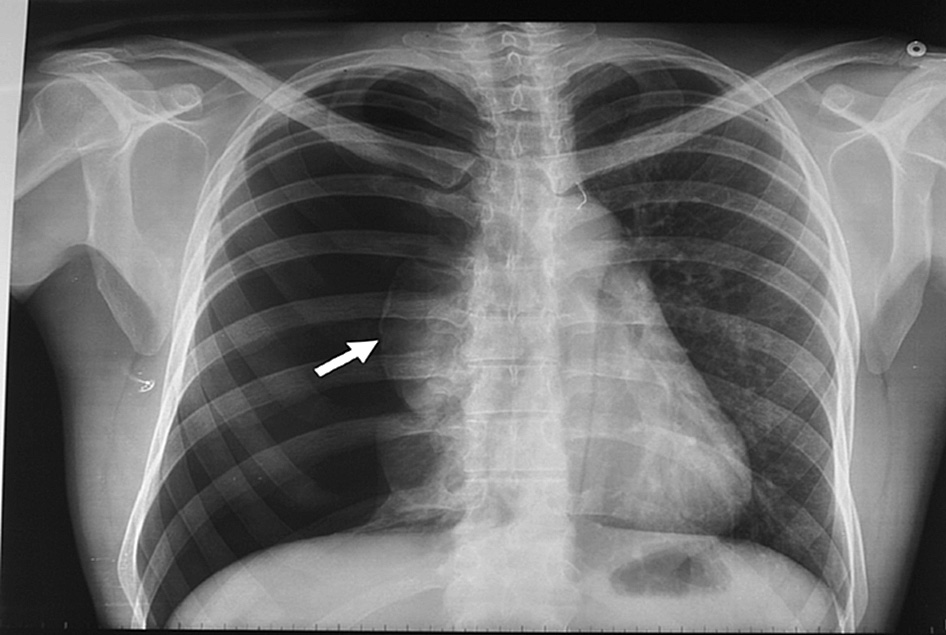

En un ensayo clínico que comparó la intervención inicial vs manejo conservador se encontró resolución del neumotórax a las 8 semanas en 98,5% vs 94,1% de los pacientes, respectivamente. New England Journal of Medicine, 30 de enero de 2020

Neumotórax espontáneo: aspiración con aguja vs drenaje con tubo

El tratamiento inicial de aspiración con aguja obtiene mejore resultados inmediatos y acorta los tiempos de internación. European Respiratory Journal, abril de 2017